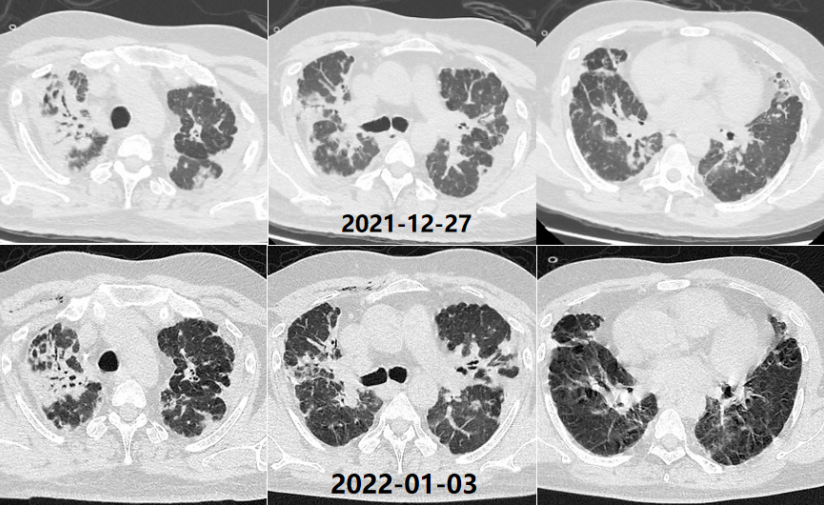

第3次住院(2020年12月7-13日):12月7日“受凉”后再次咳喘加重,于当地县医院住院。12月13日胸部CT:右肺上叶支气管束增厚,双肺胸膜下斑片影,双侧胸膜增厚,较前变化不明显(图5)。诊断为“肺炎,支气管扩张”。咳喘症状减轻,出院后继续口服醋酸泼尼松15 mg qd(图6),于2021年1月自行停药(约20 d),患者仍间断咳嗽,伴活动后气短,但可正常从事超市相关工作。

第4次住院(2021年10月24日-11月17日):2021年10月9日(停用激素后8个月)患者因“受凉”后咳喘加重,平地步行20 m即喘息明显,伴发热,体温最高38.5℃,痰中带血丝,约数口。当地诊所给予地塞米松(5 mg qd)治疗15 d,无明显改善,入当地县医院ICU住院,入院时测SpO2(未吸氧)60%。10月26日胸部CT:双肺弥漫磨玻璃影,散在斑片影,部分融合呈实变,双上肺胸膜增厚,较前明显加重(图7)。患者血气分析提示Ⅱ型呼吸衰竭,低氧血症明显,伴二氧化碳潴留,WBC和NEU升高,经治疗有所下降;生化指标可见LDH水平升高(表1~表3)。

诊断“间质性肺炎,慢阻肺急性加重期,支气管扩张,Ⅱ型呼吸衰竭”。抗感染20 d,激素治疗20 d(图9),鼻导管氧疗及NPPV。咳嗽、喘息明显减轻。胸部CT:对比10月26日,双肺斑片影、磨玻璃影明显吸收(图10)。11月17日评估病情好转出院,出院后继续口服甲泼尼龙12 mg qd(11月17-30日,13 d后自行停药)。

治疗调整(2021年12月4-19日):12月4日(停激素4 d)患者自觉喘息较前加重,再次就诊于当地市医院门诊,胸部增强CT:双肺斑片影较11月9日略吸收,双侧胸膜增厚如前(图11)。12月4日加用环磷酰胺50 mg qd至12月17日患者自行停用,并再次应用甲强龙24 mg qd,于12月18日减量至12 mg qd(图12)。

第5次住院(2021年12月20-24日):12月20日(甲强龙12 mg维持治疗中)受凉后再次出现咳喘加重,伴发热,体温38.0℃,伴肌肉、关节酸痛,流清涕,于当地市医院住院。血常规:WBC 11.46×109/L(↑),NEU 8.47×109/L,LYM 1.07×109/L,血红蛋白168 g/L,血小板327×109/L。血气分析(FiO2 0.41):pH 7.40,PaO2 115.5 mmHg,PaCO2 60.5 mmHg(↑),PFR 280 mmHg(↓),HCO3- 36.2 mmol/L。12月20日胸部CT:双肺新发散在淡薄渗出斑片影,部分结节影,较12月4日加重(图13)。予比阿培南、依替米星、莫西沙星抗感染治疗(图14),患者体温恢复正常,咳喘无改善,于12月24日转至我院。